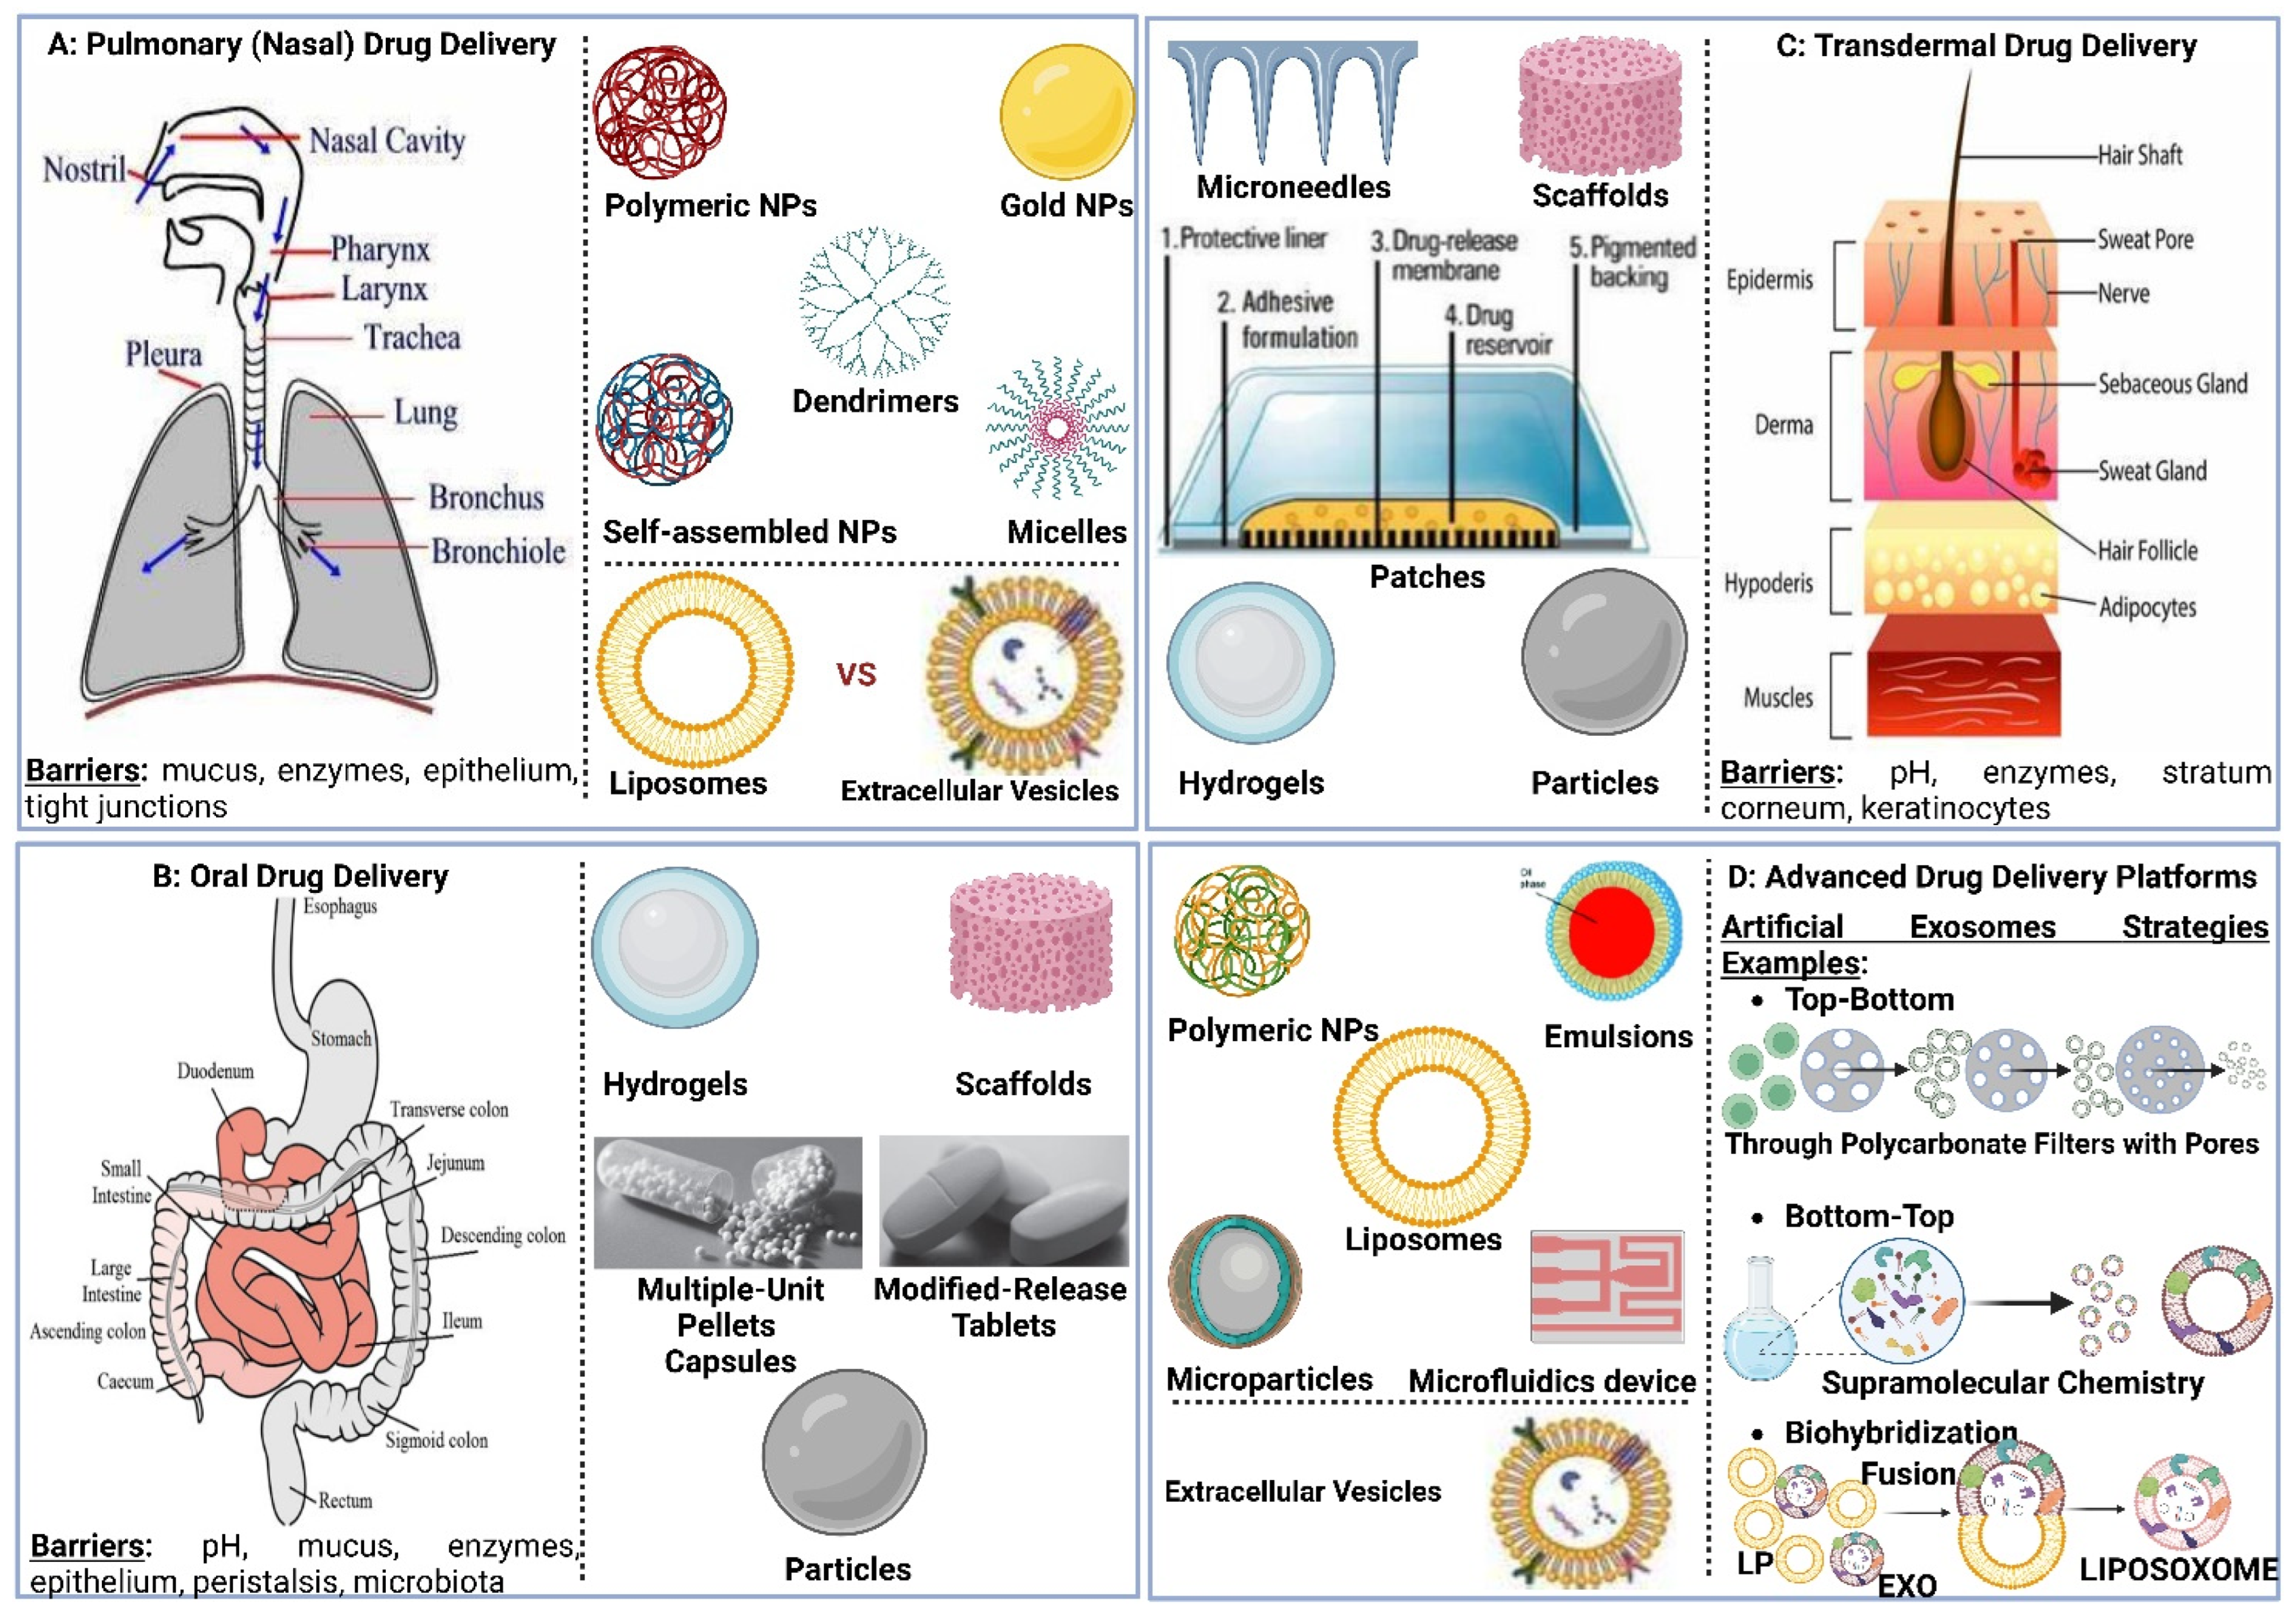

5. Pulmonary Drug Delivery

5.1. Overview of Pulmonary Drug Delivery

5.2. Requirements for Pulmonary Drug Deep Deposition

5.2.1. Inhaled Drug Formulation

Particle Size and Deposition Pattern

Particle Shape and Surface Morphology

Particle Hygroscopicity

Particle Surface Charge

5.2.2. Inhalation Drug Delivery Devices

Pressurized Metered-Dose Inhalers

Dry Powder Inhalers

Soft Mist Inhalers

Medical Nebulizers

6.1. Inhalable Liposomes

6.2. Inhalable Extracellular Vesicles

6.3. Inhalable Hybrid Vesicles